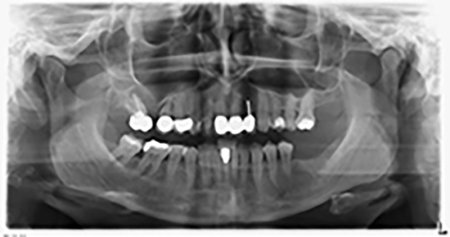

An absorbable membrane was used as the barrier in the buccal direction and covered the augmentation. Finally, saliva-proof sutures were placed (Fig. 15 to 19).

Sky implants supplied by bredent were implanted – tooth 16: 5.5 x 10mm and tooth 14: 4.0 x 10 mm.